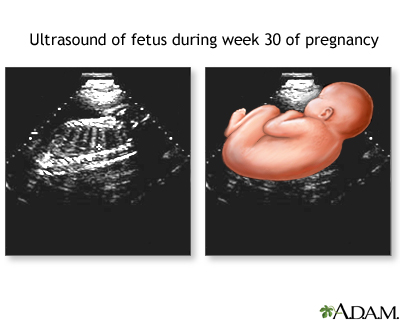

- Pregnancy